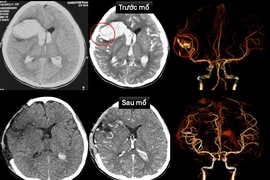

Cứu sống bệnh nhi hôn mê do vỡ dị dạng mạch máu não bị bệnh cơ tim hiếm gặp

Dị dạng động tĩnh mạch não ở trẻ em ước tính chỉ chiếm khoảng 0,01% dân số chung, 70% các trường hợp xuất huyết não tự phát ở trẻ em dưới 19 tuổi.